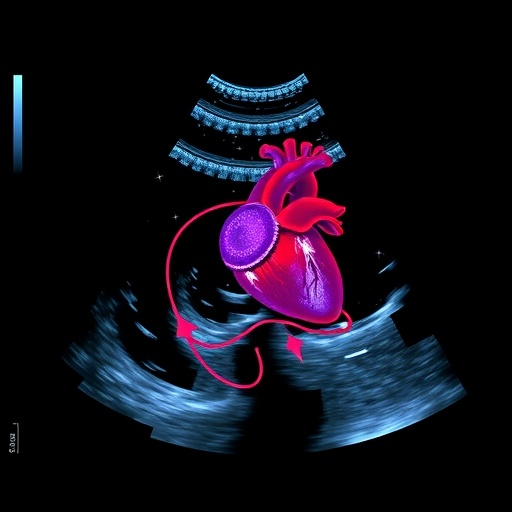

Artificial intelligence (AI) is revolutionizing the field of echocardiography, fundamentally changing how cardiovascular assessments are performed and interpreted. As the use of AI continues to expand in this area, it promises not only to enhance diagnostic accuracy but also to increase efficiency and improve patient outcomes. The integration of advanced algorithms and machine learning techniques into echocardiography holds the potential to streamline processes that traditionally relied on human expertise alone. Researchers and clinicians alike are recognizing the transformative capabilities of AI technology, paving the way for a new era in cardiovascular care.

One of the primary ways AI is enhancing echocardiography is through automation. Routine measurements and calculations that once consumed significant time and resources can now be executed by AI systems with remarkable speed and consistency. For example, AI algorithms can automate the measurement of left ventricular ejection fraction, a critical parameter in assessing heart function. By relying on AI for these standard tasks, healthcare professionals can save time, thereby allowing them to focus on more complex and nuanced aspects of patient care.

Beyond simple automation, AI’s ability to recognize disease-specific patterns offers exciting possibilities for early diagnosis. Machine learning models have been trained on extensive datasets, enabling them to identify subtle markers of cardiovascular disease that may elude even seasoned clinicians. This capability increases the likelihood of timely interventions and ultimately improves patient prognoses. As AI continues to learn from new data, its pattern recognition will grow more sophisticated, potentially surpassing the limitations of existing diagnostic classifications.

The implementation of AI in echocardiography is already unfolding in various clinical settings, showcasing its practicality and real-world impact. Hospitals and clinics are increasingly adopting AI tools to assist cardiologists in their decision-making processes, often reporting enhanced diagnostic accuracy and efficiency. Companies specializing in AI diagnostics are collaborating with healthcare organizations to integrate these technologies, leading to innovative solutions that improve the standard of care for patients with cardiovascular diseases.

Looking ahead, the future of AI in echocardiography is promising, with ongoing research and development aimed at further enhancing its capabilities. Innovations such as real-time machine learning, which could enable AI to learn from live echocardiographic data, are on the horizon. This advancement may provide clinicians with instantaneous insights and recommendations, revolutionizing how echocardiograms are conducted and interpreted.